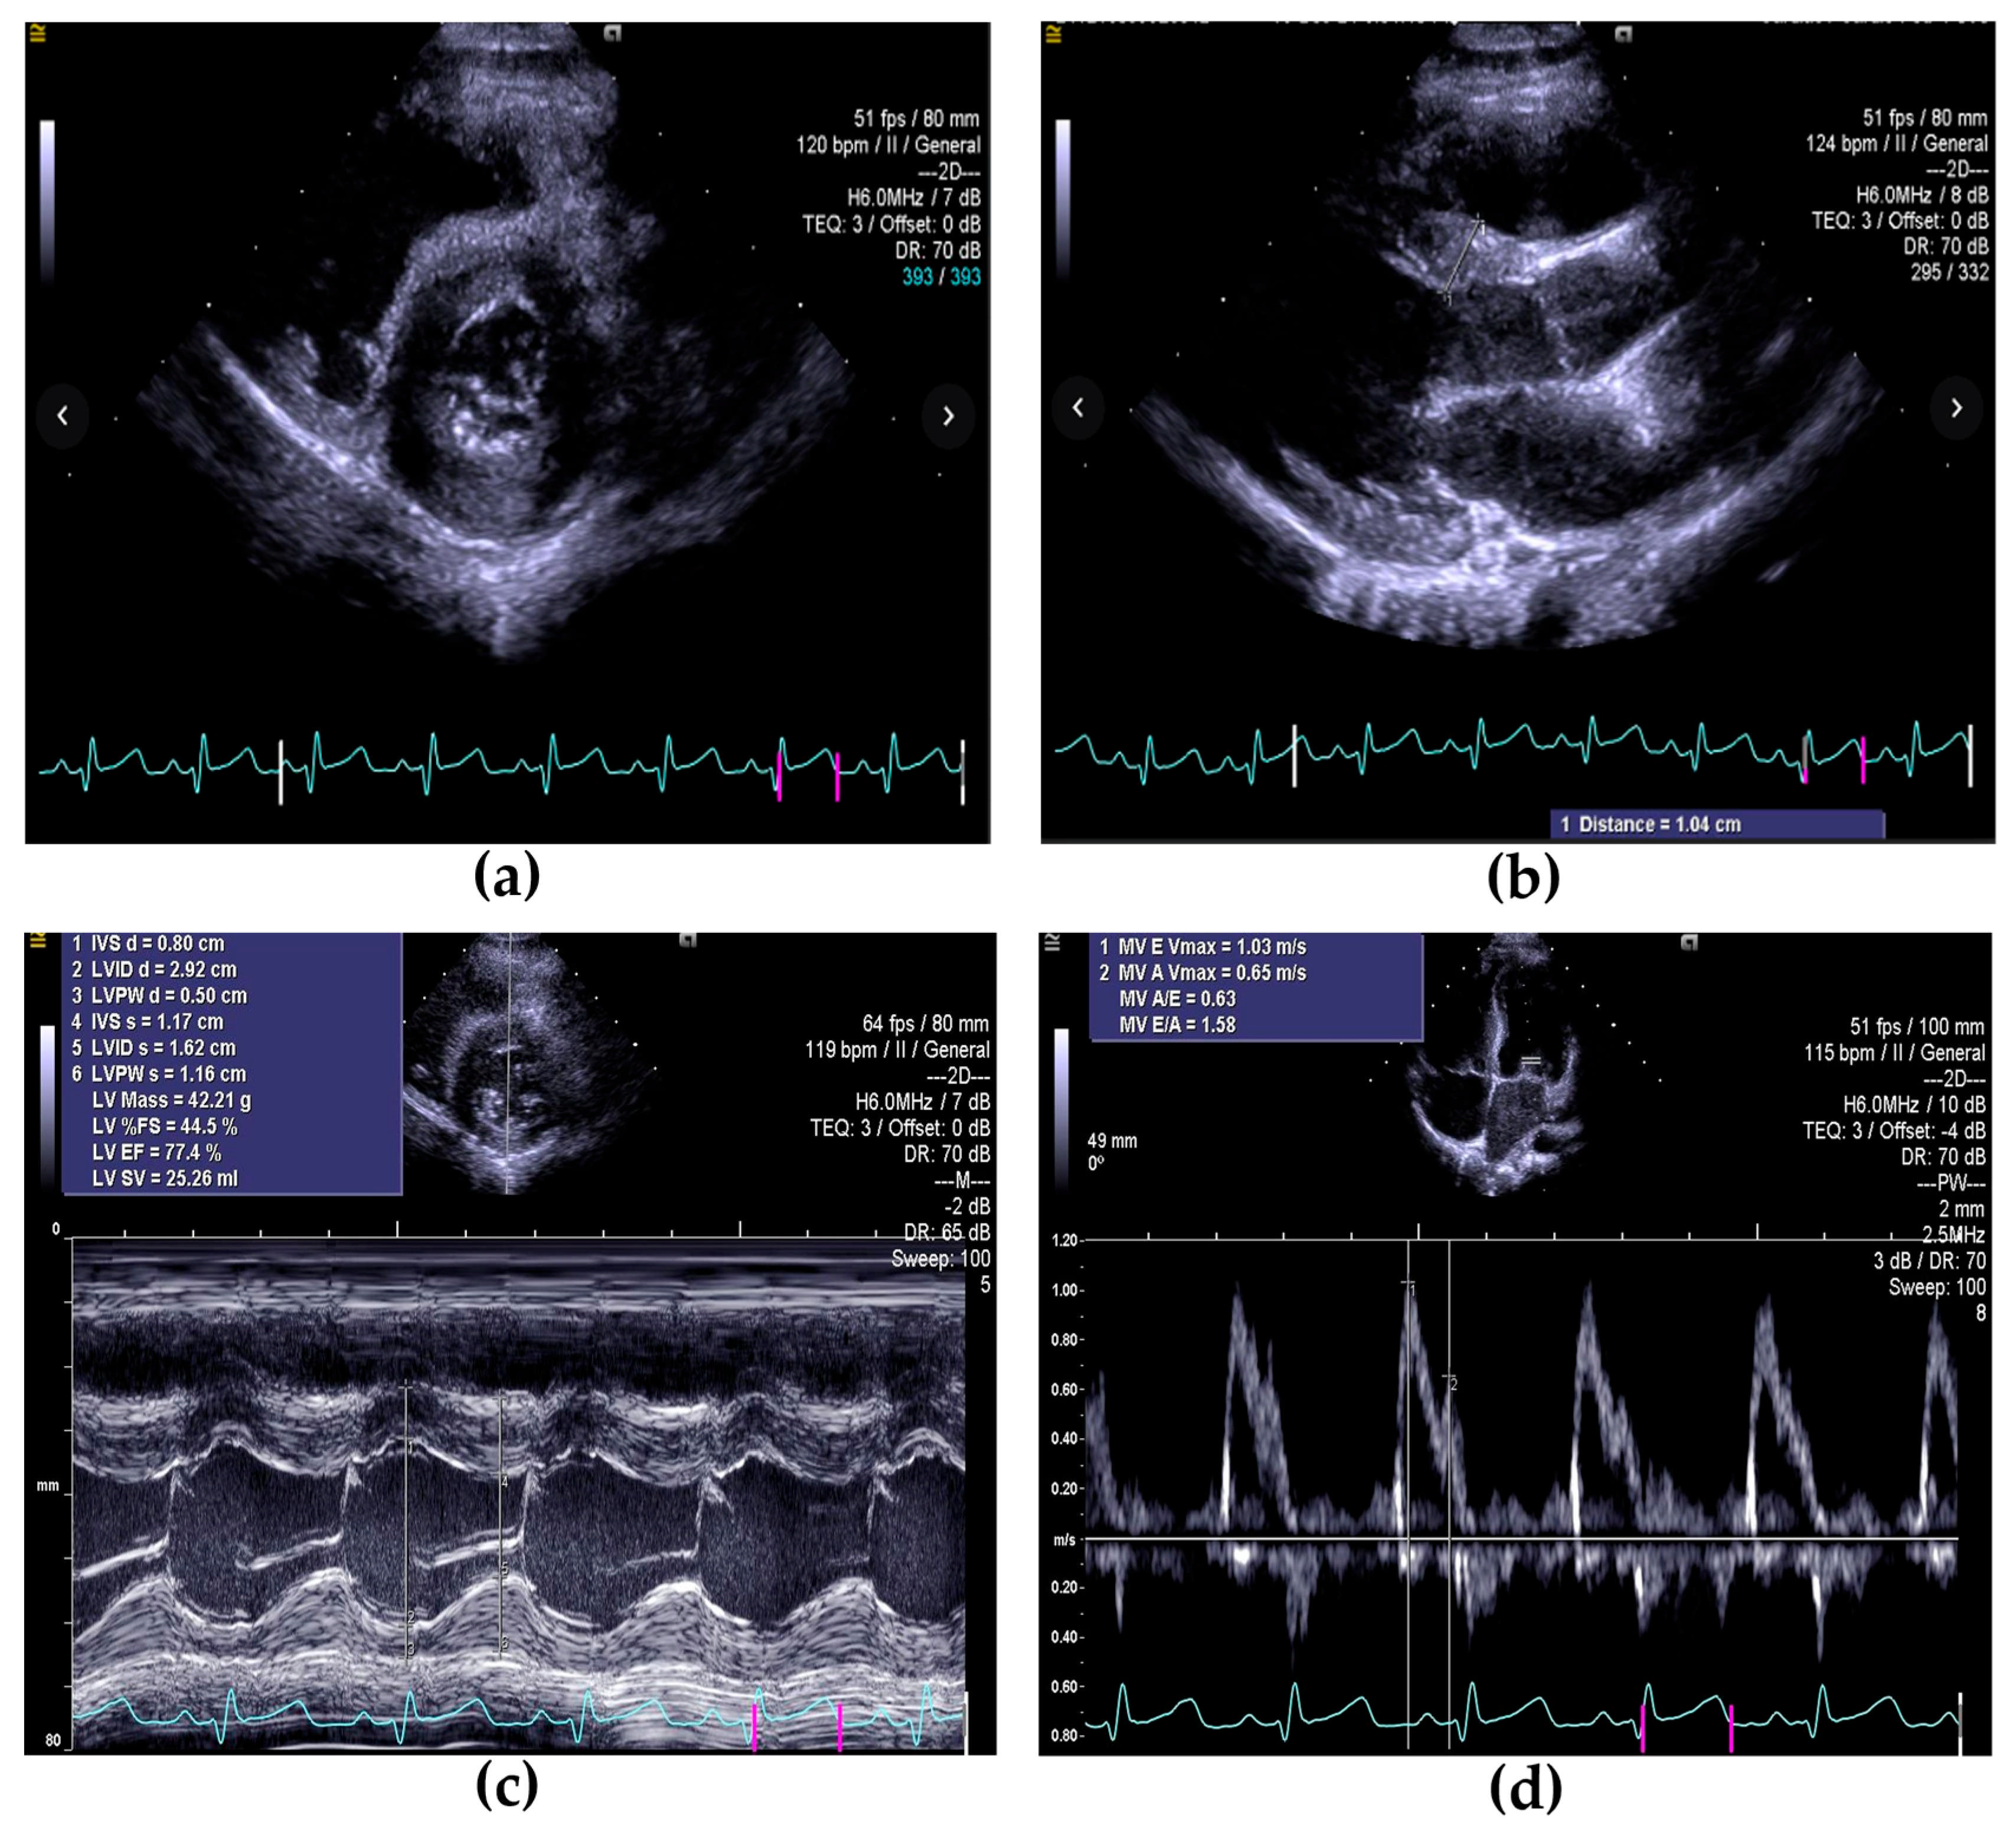

Case Presentation